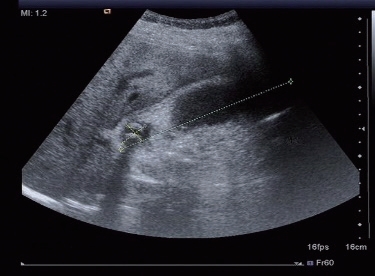

1)充填型胆囊结石。位于胆囊窝的正常胆囊液性透声腔消失,胆囊轮廓的前壁呈弧形或半月形光带,胆囊腔被不规则的强回声及后方的宽大声影取代,胆囊的后壁完全不显示。这种现象简称为囊壁结石声影三合征,即WES征(图5-9)。注意不要与肠气回声相混淆造成漏诊、误诊。

图5-9 充填型胆囊结石(WES征)

图5-14 胆总管结石(强光团处)并扩张呈双筒猎枪征

CBD:胆总管;PV:门静脉;LIVER:肝。

(1)肝外胆管扩张,与门静脉主干形成双筒猎枪征(图5-14)。扩张的胆管壁可增厚,回声增强,内壁欠光滑。结石部位在胆囊管以上者胆囊不增大;结石部位在胆囊管内或以下胆管者胆囊增大;结石在胆总管则可以引起整个胆管系统的扩张。

(2)管腔内出现形态稳定的高/强回声团,与胆管壁间分界清楚。

(3)强回声团后方可见声影。